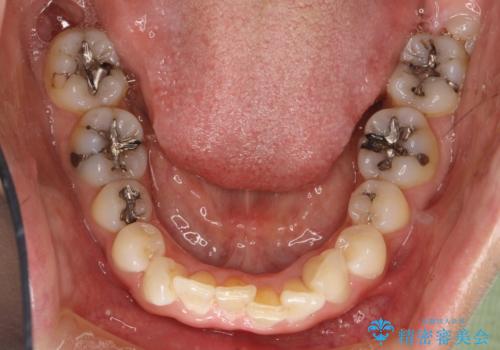

- 前歯のがたつきを気にされて来院されました。

右上の前から2番目の歯が前方に大きく傾いており、下の前歯もガタガタしていました。

インビザラインにて、歯と歯のあいだをわずかに削り並べる計画としました。

しっかりとマウスピースを使用していただけたので、順調に治療を終えることができました